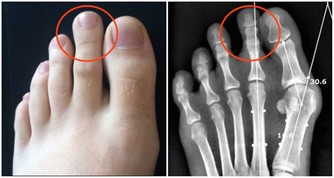

結果發現,高糖飲食的非酒精性脂肪肝患者脂肪代謝過程發生了變化,這些變化帶來的後果是患心髒病或者中風的風險更大了。原本肝臟脂肪含量較低的男性在一段時期的高糖飲食過後,肝臟脂肪含量有所升高,其體內脂肪代謝發生了類似於非酒精脂肪肝患者的變化。研究得出的結論是,攝入過量的糖會改變脂肪代謝,增加患心髒病的風險,即使只是一小勺糖,只要超過了正常攝入量,對人的影響就可能是致命的。

目前,非酒精脂肪肝的患病率在兒童和成人中都有所上升。兒童和青少年更喜歡碳酸飲料和糖果,糖的攝入量也很容易超標,考慮到兒童和青少年中非酒精脂肪肝的高患病率,我們要引起對年輕人群未來健康的關注。